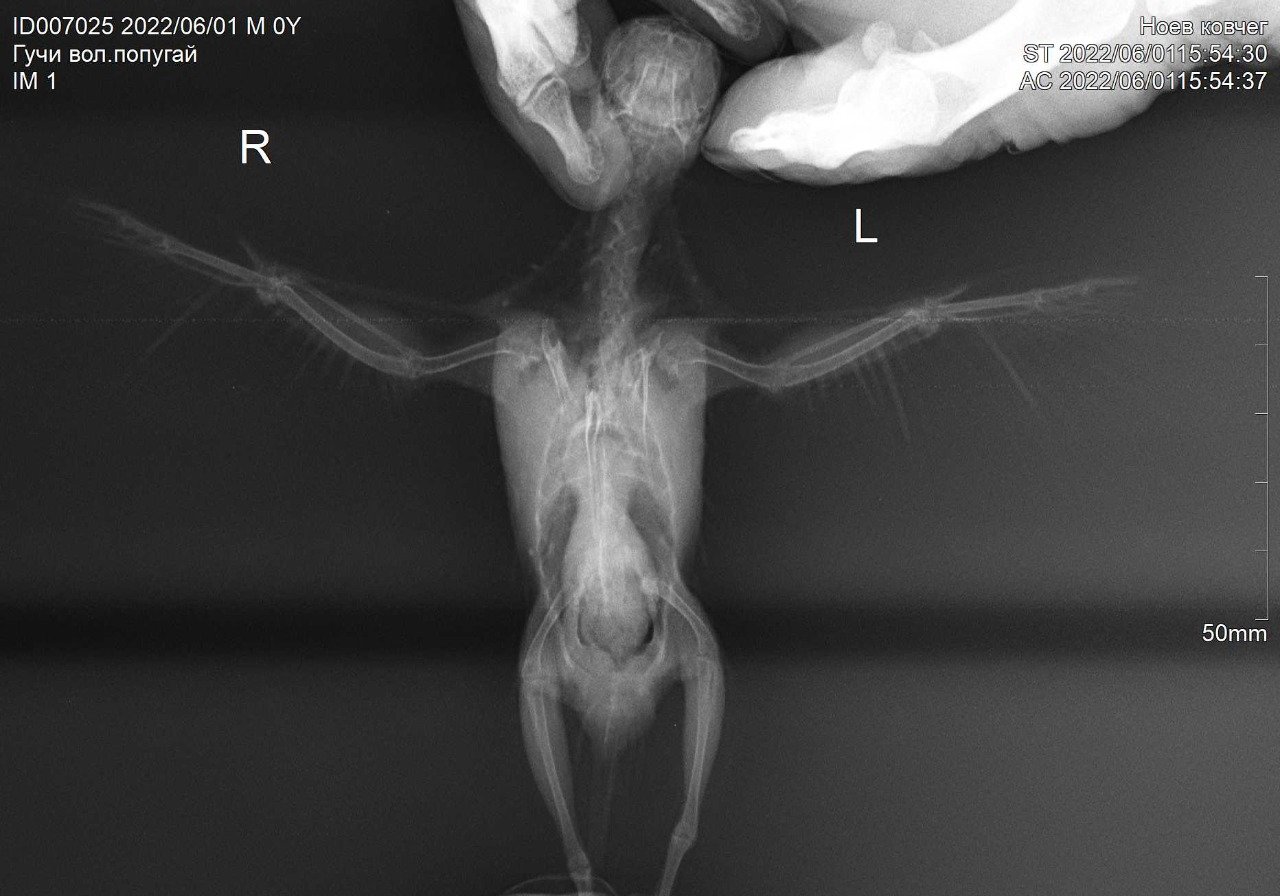

5. Здравствуйте! Решила все-таки создать тему про лечение птицы из этого поста. У нас, помимо физических повреждений, нашли ещё кучу всего. Вообще бедный птен, похоже, пока его не подобрали, с поврежденным крылом и лапкой еще неделю на улице выживал, питаясь непонятно чем и подмерзая( Полный список диагнозов пока: кандидоз, кокцидиоз, трихомоноз (хотя наростов нет, но нашли трихомонаду в анализе кала), гепатоз (на рентгене печень очень сильно увеличена, как сказали, может быть результатом трихомоноза как раз), аэросаккулит (под вопросом). Плюс вывих правого плечевого сустава и закрытый перелом бедра. Назначили лечение: 1. Флуконазол 50 мг ? капсулы в 1 мл воды, выпаивать по 0,3 2 р.д. 14 дней. 2. Мелоксикам 7,5 мг ? таблетки в 1 мл воды выпаивать по 0,6 2 р.д. после еды 3. Гептрал или Самеликс 1/10 таблетки с едой 4. Стоп-кокцид 2,5% 0,18 мл однократно (уже дали, на следующей неделе повторно сдадим анализ) 5. Амоксиклав суспензия по 0,4 мл 2 р.д. 14 дней (подключить на след. неделе) 6. Метрогил 5 мг/мл 0,5 мл 2 р.д. + витамины и кальция глюконат Сдали анализы на псевдотуберкулез, хламидиоз, микоплазмоз и сальмонеллез. Первые три все пришли отрицательные, последний еще ждем, но его сдавали скорее для галочки – помет не сальмонельный и особых подозрений на нее и не было. Не смотря на такой букет, птиц достаточно активный и бодрый, первое время, конечно, лежал-боялся, сейчас осмелел, чистит перья, делает зарядку и отчаянно пытается урчать и бить меня крылом, стоит мне полезть к нему, чтобы покормить, поменять подстилку или дать лекарства. Вопросы у меня такие: лечение кажется адекватным, но прям очень много всего… не добьем ли мы так печень окончательно, даже под прикрытием гептрала? К тому же меня сильно беспокоит вес птички… когда подобрали, он был 230 грамм. При последнем взвешивании – 220. При этом ест птица сама и хорошо (хотя сейчас и не так жадно, как первые дни), еда, судя по анализам, переваривается, и зерно из зоба уходит, хотя и чуть медленнее, чем должно быть – за часа 3-3,5. Так почему худеет? Это следствие инфекций и нужно сперва бороться с ними и тогда вес сам наладится? Или стоит докармливать, пусть даже и насильно? Ну и вообще – может, будут какие-то общие рекомендации? И какие вообще шансы у птицы с таким набором всего? P.S.: Прилагаю фото птички и помета. Всё снято сегодня. Чуть позже попробую приложить рентген, если смогу открыть диск.